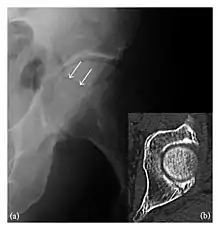

High-energy trauma fractures

Occult osseous injuries may result from a direct blow to the bone by compressive forces of adjacent bones against one another or by traction forces during an avulsion injury. Lesions in the tibial plateau, hip, ankle, and wrist are often missed. In a tibial plateau fracture, any disruption of the posterior and anterior cortical rims of the plateau should be sought. Impaction of subchondral bone will appear as an increased sclerosis of the subchondral bone (Figure 1). In the hip, posterior acetabular fractures also present subtle radiographic findings. The acetabular lines should then be carefully examined keeping in mind that the posterior rim, which is harder to see on X-rays, is more frequently fractured than the anterior rim (Figure 2). In the wrist, detection of carpal bone fractures is often challenging, with up to 18% of scaphoid fractures radiographically occult. Carpal fractures, especially the scaphoid, are associated with the risk of avascular necrosis. In apparently normal wrist radiographs from symptomatic patients, if there is history of a fall on an outstretched hand with pain in the anatomic snuffbox, suggesting scaphoid injury, the initial examination with posteroanterior, lateral, and pronation oblique views must be complemented by other specific views such as supination oblique and the "scaphoid" view A careful examination of cortices for evidence of discontinuity or offset and cancellous bone for lucency is necessary (Figure 3).[1]

a

b

c

Figure 3: A 26-year-old man presenting with wrist pain after being assaulted. (a) Initial anteroposterior radiograph shows a subtle linear lucency within the scaphoid extending to the scaphocapitate articular surface that was overlooked (arrow). (b) Initial "scaphoid" view was negative. (c) Followup anteroposterior radiographs, 12 days later, shows obvious scaphoid fracture (arrows).[1]

Triquetral fracture usually occurs on the dorsal aspect by impingement from the ulnar styloid or avulsion of strong ligamentous attachment. The dorsal avulsion fracture or "chip fracture" appears as a small bony fragment on the dorsal aspect of the triquetrum and is best detected on the lateral view(Figure 4). When radiography is negative in patients with high suspicion of a fracture, both MRI and MDCT will be of value. However, it has been shown that MRI is superior for detecting trabecular fractures in carpal bones.

Figure 4: Dorsal triquetral fracture of the left wrist in a 30-year-old man after a trauma. (a) Anteroposterior radiograph shows a normal appearance. (b) Lateral radiograph of the same wrist demonstrates a chip fracture off the dorsal aspect of the triquetrum (arrow).[1]